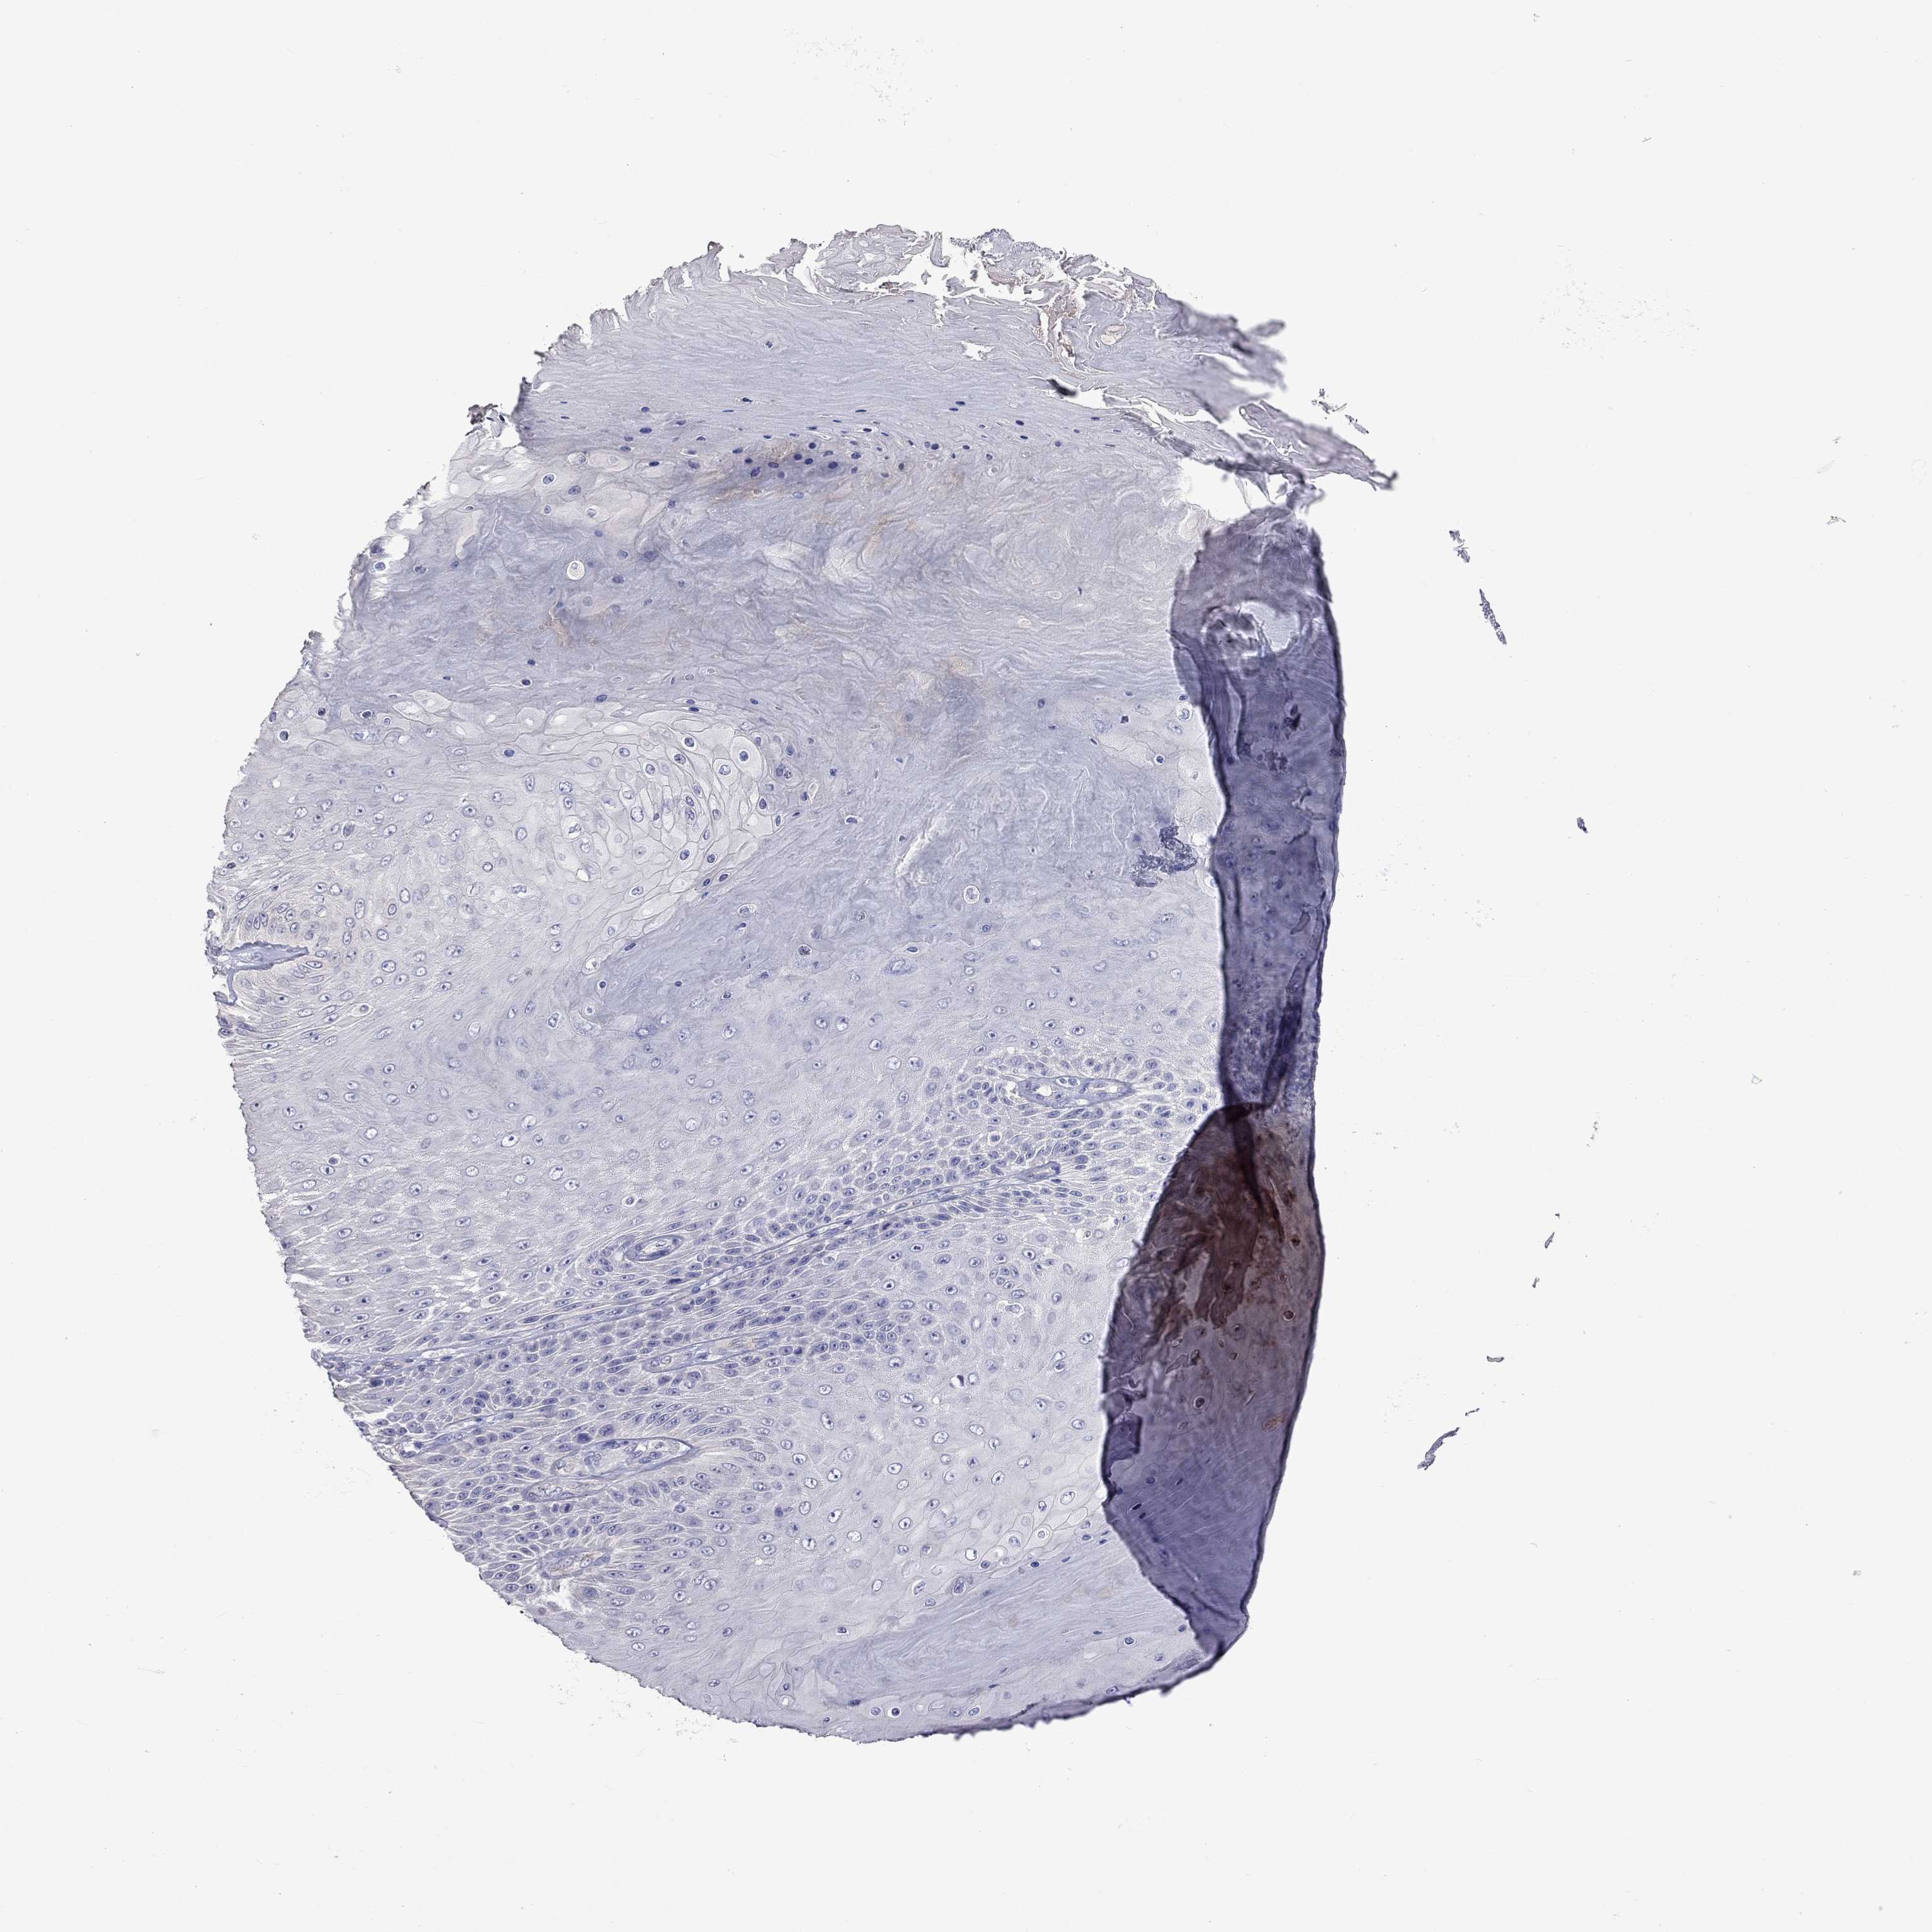

CANCER SKIN CANCER Show tissue menu

Basal cell and squamous cell cancer

SKIN CANCER - Protein expressioni

A mouse-over function shows sample information and annotation data. Click on an image to view it in a full screen mode. Samples can be filtered based on level of antibody staining by selecting one or several of the following categories: high, medium, low and not detected. The assay and annotation is described here.

Each image is clickable and will lead to virtual microscopy that enables deeper exploration of all samples and also displays staining intensity scores, fraction scores and subcellular localization as well as patient and tissue information for each sample.

Antibody HPA076844

Basal cell carcinoma

Squamous cell carcinoma, NOS